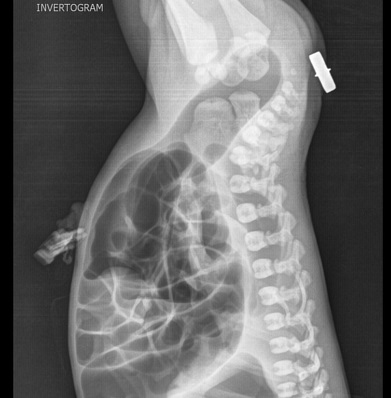

Une autre cas de

imperforation anale avec cliche de profile decubitus

ventral position"priera Mahometa" avec rayon central

expose horizontale . La colon sigmoide est distendue

en plein de gaz |

Invertogram : Technicque

radiologique sans preparation a position

inverse ( voie image ) avec cliche expose de face et

de profile . Une piece de metal etre place en dehord de anus

. Il y avaite deux forme de malformation : les hautes ( 55%)

s'il la distance du cul de sac du colon terminal a l'anus

depasse de plus > 2 cm , ce type est souvent en associe avec

les autres malformations : urogenitale ( fistule ) ,

rachidienne ( spina malformation ) et cardiaque . Les basses

( 45%) s'il la distance du cul de sac et anus est a moindre

< 2cm et ce forme avait de bon prognostic que la forme

haute

Le nouveau ne se met en

position inverse a profile et une piece de metal

etre en place au milieur des deux fesse pres d'anus

. Le cliche doit expose seul apres trois

minute de repose a cette position |

Cliche de profile en

position " priera Mahometa " . Le rayon X central

est enplace a horizontal , la cassette est place

perpendiculaire avec la table ( voie en image )

. |